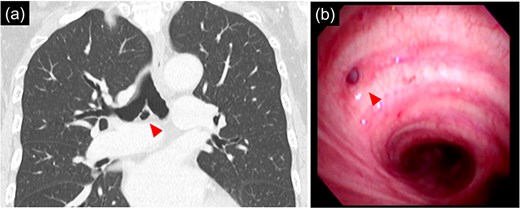

Bronchoscopy after intubation revealed an orifice of the BD in the cartilage of the right main bronchus with two rings below the carina (Fig. 2). First, a lower mediastinal lymph node dissection and BD were performed. The area around the BD was prone to bleeding and the lymph nodes were in close contact with each other (Fig. 3), making it difficult to separate them from the BD. After identifying and exposing the stalk of a BD, ligation of the diverticulum with ENDOLOOP® PDS II Ligature allowed for control of bleeding and the lymph nodes could be safely removed from the BD (Video 1).

Intraoperative images of the inferior mediastinal region. (a) Image of dissecting the bronchial diverticulum and mediastinal lymph nodes. (b) Image of a bronchial diverticulum after ENDOLOOP® PDS II Ligature ligation. Arrowhead: bronchial diverticulum.

After lymph node dissection was complete (Fig. 3), the BD was additionally ligated. The #11i LN was enlarged but without invasion, and there was no lymph node metastasis on frozen pathology. Following a conventional right lower lobectomy, the BD and lower lobe bronchial stumps were covered with pericardial fat tissue. The patient was discharged without postoperative complications. No lymph node metastases were found pathologically in the other dissected lymph nodes, and the diagnosis was p-T1bN0M0 stage IA2. Chest CT 6 months after the operation showed no recurrence of lung cancer; however, air was detected in the BD, suggesting an opening of the diverticulum.